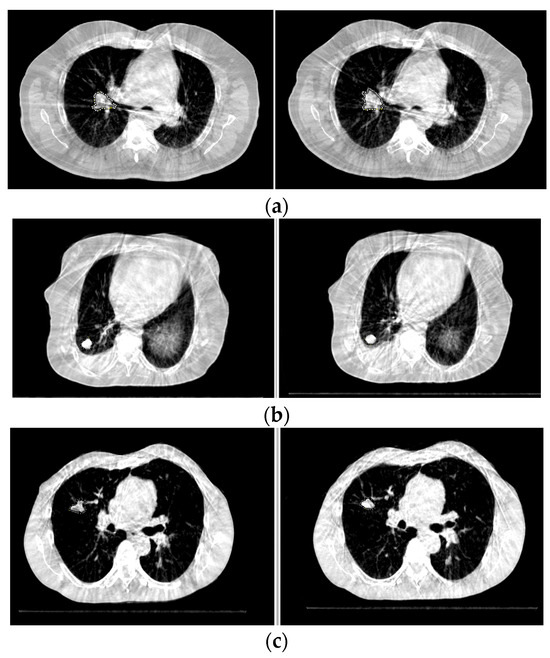

2.2. Image Analysis

2.3. Tumor Response Evaluation Parameters

2.4. Radiologic Assessment of Tumor Response